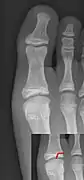

Salter–Harris IV fracture of big toe proximal phalanx.